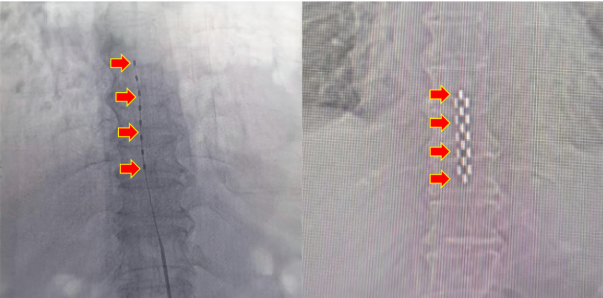

近日,重庆医科大学附属璧山医院(重庆市璧山区人民医院)通过多学科协作,成功为一名合并多种心肺疾病的患者实施“体外循环下主动脉瓣置换+二尖瓣成形+房颤射频消融(改良迷宫)+左心耳闭合+卵圆孔闭合+右肺上叶亚肺叶切除”高难度联合手术,展现了医院多学科诊疗(MDT)模式下处理复杂疾病的综合实力。